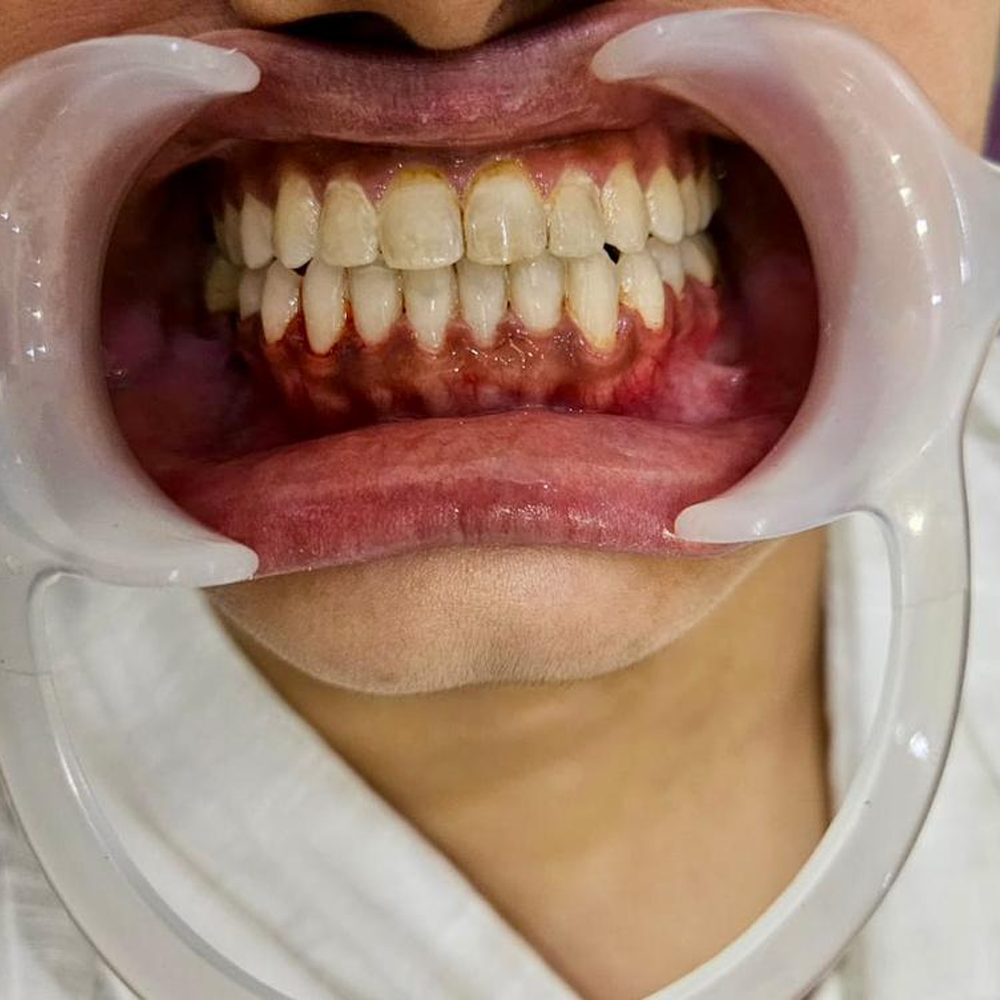

Orthognathic Surgeries

A forward or backward placed upper or lower jaw can have an immense impact on an individual’s oral health, personality and social life. These are known as skeletal malocclusion. In an age where certain jobs require a certain facial profile, such malocclusions can be a deterrent.

Orthognathic surgery answers these problems along with orthodontic therapy.

Utilizing these surgical techniques we can move a forwardly placed jaw backward and vice-versa.

At our center, we strive to diagnose such malocclusion and do orthognathic surgeries if required.